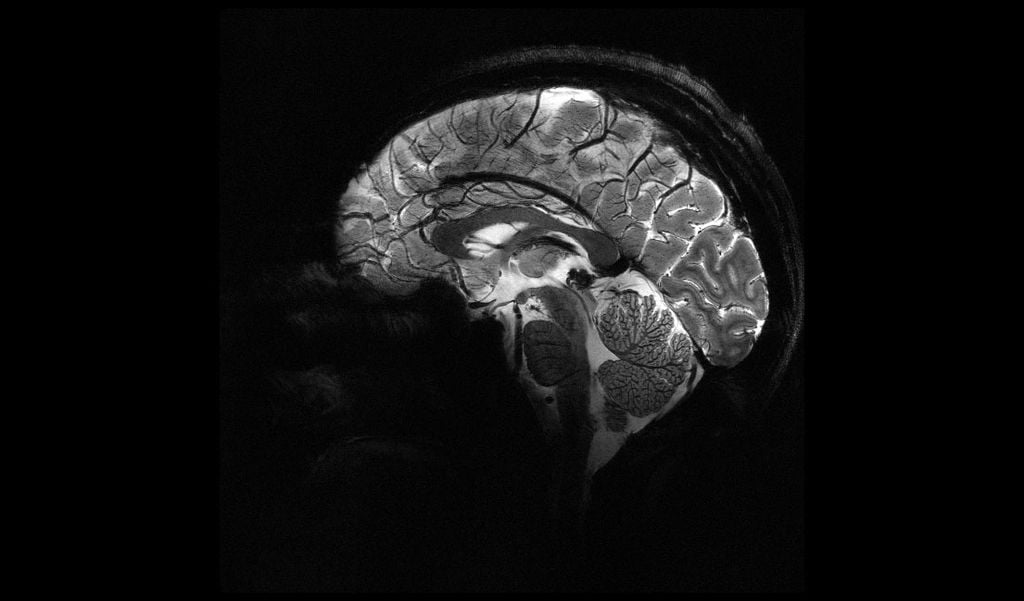

Os aparelhos de ressonância magnética usam poderosos ímãs, com potências de 1,5 tesla ou 3 tesla, que criam campos magnéticos. Em especial, esses ímãs provocam o alinhamento dos prótons de hidrogênio, presentes nos tecidos moles (ricos em água e/ou gordura).

Em paralelo, ondas de radiofrequência são liberadas na parte do corpo que se busca analisar, perturbando esse alinhamento. Conforme os prótons se movimentam, eles emitem sinais (ondas de rádio) e estes são captados por softwares, capazes de transformar esses dados em imagens.